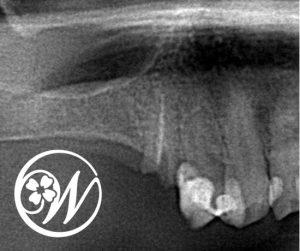

患者様は50歳代女性で、「右上5番の被せ物が外れた」という主訴で来院されました。

精密検査(レントゲン・CT)を行った結果、右上5番は残根状態で保存が困難、さらに右上6番はすでに欠損している状態であることが分かりました。

また、奥歯2本が機能していないことで、噛み合わせのバランスが崩れ、今後ほかの歯に負担がかかるリスクも高い状態でした。